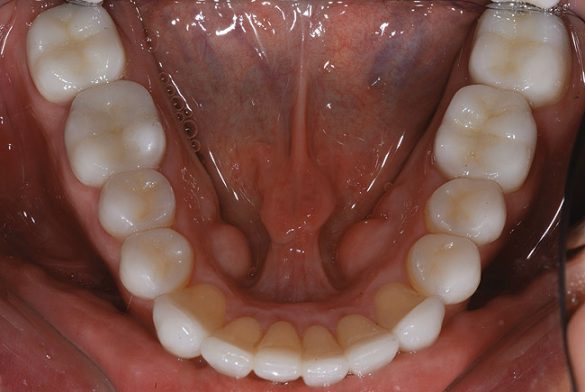

Un bărbat în vârstă de 48 ani, clinic sănătos, s-a prezentat pentru consultaţie, reclamând în principal zâmbetul său dezagreabil. Era îngrijorat cu privire la pierderea progresivă a structurii dentare pe care a constatat-o în decursul ultimilor ani şi cu privire la colorarea generalizată şi afişarea inadecvată a dinţilor şi gingiilor sale. Imaginile retractate preoperatorii relevau o formă de arcadă îngustă cu înghesuire minoră, uzură severă şi eroziune, alături de formarea unor torusuri voluminoase în regiunile maxilare vestibulare1 (fig. 1).

Spre deosebire de amprentele tradiţionale din polivinil-siloxan (PVS) în care toţi dinţii restauraţi trebuie retractaţi şi izolaţi în acelaşi timp, aparatul de scanare orală permite capturarea, la nevoie, a secţiunilor. După finalizarea amprentării digitale, în câteva zile modelele SLA răşinoase se recepţionează de laborator, se aplică pinuri, se secţionează şi sunt pregătite de montare şi fabricarea restaurărilor restante (fig. 7).